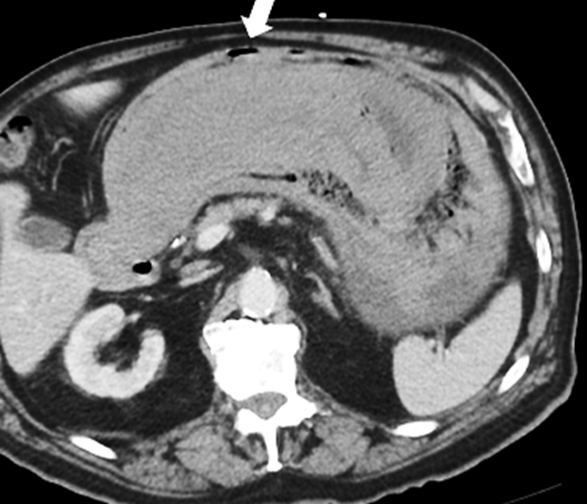

Figure 3: Axial CT of EG

Irregular fold thickening, perigastric fat stranding, focal intramural gas; suggests septic inflammation.